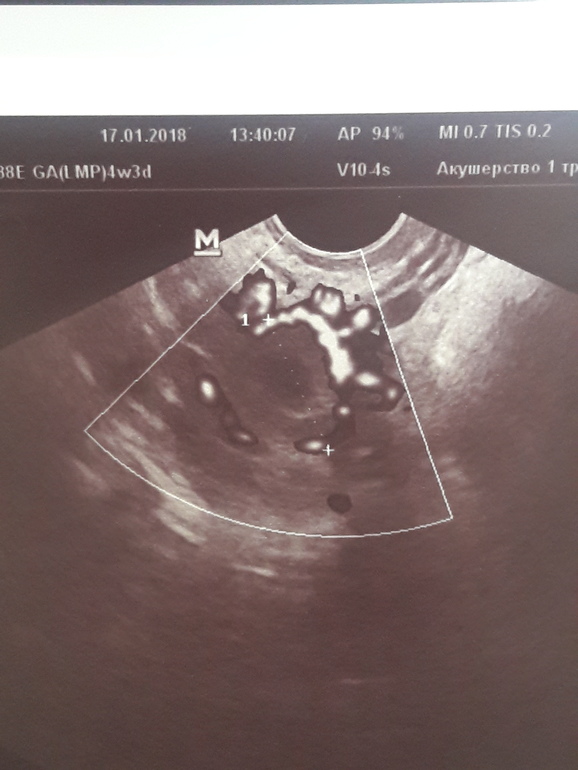

вот-подтвержденное ЖТ.(правда оно беременное,пара дней задержки).Светящиеся области вокруг-кровоток..

нашла еще пару подтвержденных ЖТ,но это уже не беременные))